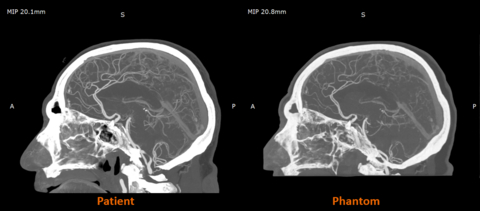

据悉,这种防透射材料已在英国与包括CPI和博蒙特医院在内的合作伙伴开展的合作研究项目中得到应用,展现了临床和教育领域的应用潜力。诸如脑血管造影模型等不透射线的3D打印模型,有助于提高培训的逼真度,并为影像研究创造可重复的环境。

Stratasys 与西门子医疗合作的早期研究结果表明,RadioMatrix 人体模型能够以极高的精度在 CT 成像中复制人体组织,即使在灰质和静脉等敏感区域,偏差也仅为 1 个亨氏单位 (HU)。结合Stratasys 的数字解剖技术和先进的成像算法,最终生成的模型既保留了解剖和病理细节,又为基于尸体的培训提供了一种一致且符合伦理的替代方案。预计这些模型将帮助放射科医生改进和验证 CT 扫描方案,同时加快高级成像算法的创建,从而实现更准确的诊断和治疗计划。

△人体CT扫描与Stratasys公司3D打印模型CT扫描对比。图片来自Stratasys公司。